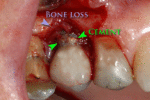

From these theoretical risks, derive the real world complications. Long-term failures are due to either loss of bone around the tooth and/or gingiva due to peri-implantitis or a mechanical failure of the implant. Because there is no dental enamel on an implant, it does not fail due to cavities like natural teeth. While large-scale, long-term studies are scarce, several systematic reviews estimate the long-term (five to ten years) survival of dental implants at 93–98 percent depending on their clinical use.[1][2][3] During initial development of implant retained teeth, all crowns were attached to the teeth with screws, but more recent advancements have allowed placement of crowns on the abutments with dental cement (akin to placing a crown on a tooth). This has created the potential for cement, that escapes from under the crown during cementation to get caught in the gingiva and create a peri-implantitis (see picture below). While the complication can occur, there does not appear to be any additional peri-implantitis in cement-retained crowns compared to screw-retained crowns overall.[40] In compound implants (two stage implants), between the actual implant and the superstructure (abutment) are gaps and cavities into which bacteria can penetrate from the oral cavity. Later these bacteria will return into the adjacent tissue and can cause periimplantitis. As prophylaxis these implant interior spaces should be sealed.[41]